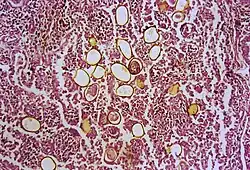

| Photomicrograph showing ova within lung parenchyma | |